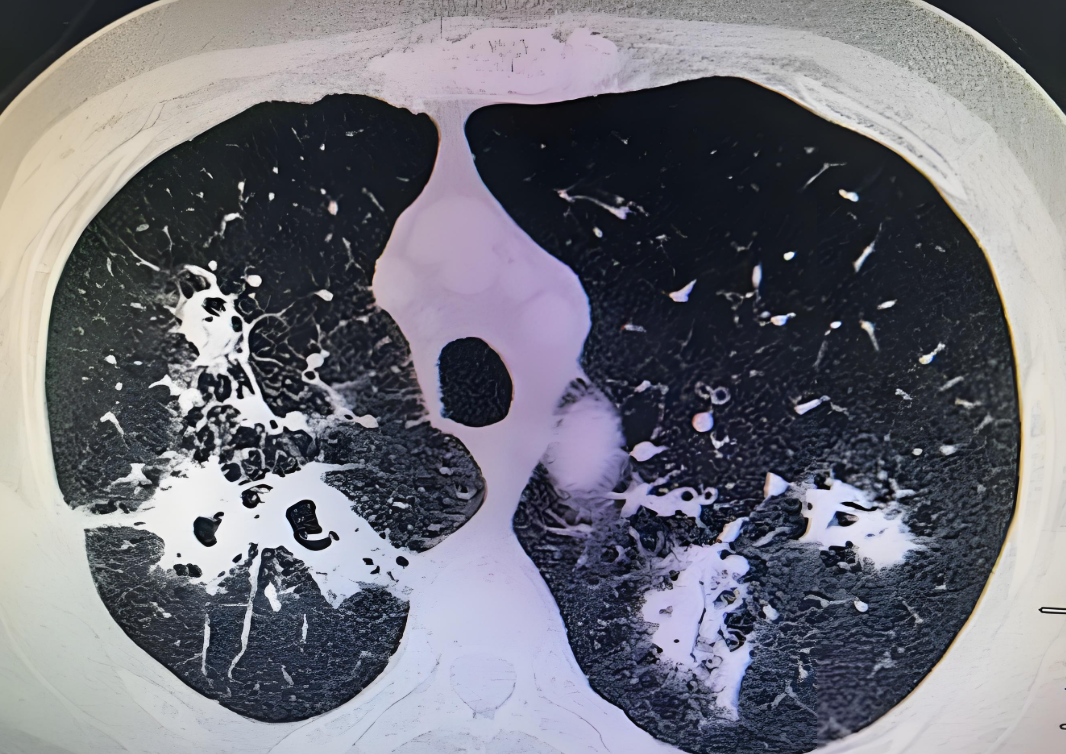

狗狗肺气肿的症状1早期症状不明显,只是在过度劳累的情况下会出现呼吸困难的症状2轻度肺气肿患者的体征多无异常,病情加重时会出现呼吸运动减弱桶状胸呼气延长肝浊音界下降语颤音减弱或消失呼吸音减弱肺部有湿啰音3有时肺底可闻及干湿啰音,肺动脉第二心音亢进唯一不同的事。

早期可无症状,或仅在劳动运动时感到气短,随着肺气肿的进展呼吸困难程度随之加重,以至稍一活动,甚或完全休息时仍感气短患者还可存在乏力体重下降食欲减退上腹胀满肺气肿的治疗在没有症状时是不需要治疗的,一旦出现了呼吸困难的症状,可以应用支气管舒张剂进行治疗,例如长效的β2受体激动。

肺气肿的症状表现多样,其严重程度依肺气肿的程度而异,主要包括以下几点气短早期可能仅在体力活动或运动时感到气短,随着肺气肿的发展,即使在轻微活动或完全休息时也会感到气短全身症状如乏力体重下降食欲减退等,这些症状可能随着病情的加重而逐渐明显呼吸道症状咳嗽和咳痰,咳嗽可能表现为。

肺气肿的严重程度因病情阶段而异初期阶段症状较轻在肺气肿初期,患者通常只在进行比较累的活动或大量体育活动时,会出现耐力下降胸闷气短的现象日常生活无严重影响此阶段对患者的日常生活影响不大加重阶段活动耐力下降随着肺气肿的逐渐加重,患者的活动耐力和劳动能力会进一步下降,开始。